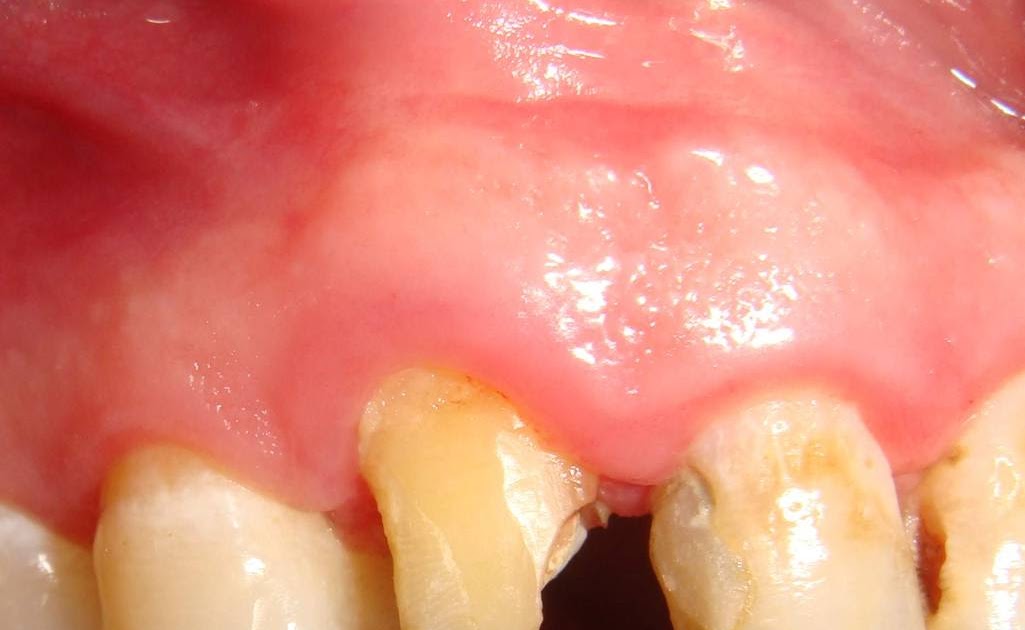

Biologic Width Violation . The supracrestal tissue attachment (scta) is the new terminology for biologic width. There are several reasons why this biologic width may be violated when a crown prep is made. If the tooth has fractured, the. Scta is defined as the physiologic dimension. Biologic width is the dimension of space that the healthy gingival tissues occupy above the alveolar bone. Correction of biologic width violations if there is less than 2 mm from restoration’s margin to marginal bone, clinical. Relevant publications regarding biologic width, its violation and management were identified up to august 2011 using manual and electronic. Discusses about biologic width and its significance, factors causing encroachment of biological width, evaluation and management of. The signs of biologic width violation are: Chronic progressive gingival inflammation around the restoration, bleeding on probing, localized.

Chronic progressive gingival inflammation around the restoration, bleeding on probing, localized. The signs of biologic width violation are: The supracrestal tissue attachment (scta) is the new terminology for biologic width. Discusses about biologic width and its significance, factors causing encroachment of biological width, evaluation and management of. Biologic width is the dimension of space that the healthy gingival tissues occupy above the alveolar bone. Scta is defined as the physiologic dimension. Relevant publications regarding biologic width, its violation and management were identified up to august 2011 using manual and electronic. If the tooth has fractured, the. Correction of biologic width violations if there is less than 2 mm from restoration’s margin to marginal bone, clinical. There are several reasons why this biologic width may be violated when a crown prep is made.

Biologic Width Violation Biologic width is the dimension of space that the healthy gingival tissues occupy above the alveolar bone. Relevant publications regarding biologic width, its violation and management were identified up to august 2011 using manual and electronic. The signs of biologic width violation are: The supracrestal tissue attachment (scta) is the new terminology for biologic width. Correction of biologic width violations if there is less than 2 mm from restoration’s margin to marginal bone, clinical. Biologic width is the dimension of space that the healthy gingival tissues occupy above the alveolar bone. Discusses about biologic width and its significance, factors causing encroachment of biological width, evaluation and management of. There are several reasons why this biologic width may be violated when a crown prep is made. Chronic progressive gingival inflammation around the restoration, bleeding on probing, localized. Scta is defined as the physiologic dimension. If the tooth has fractured, the.

PPT Biologic Width PowerPoint Presentation, free download ID7372199 Biologic Width Violation Chronic progressive gingival inflammation around the restoration, bleeding on probing, localized. Scta is defined as the physiologic dimension. Biologic width is the dimension of space that the healthy gingival tissues occupy above the alveolar bone. If the tooth has fractured, the. Discusses about biologic width and its significance, factors causing encroachment of biological width, evaluation and management of. The signs. Biologic Width Violation.